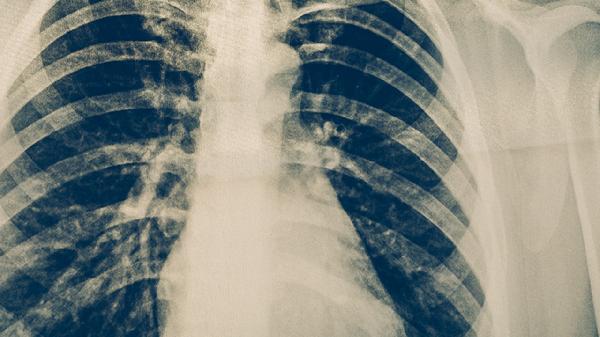

預防肺結(jié)核疾病可通過接種卡介苗、保持良好通風、避免密切接觸患者、增強免疫力、定期篩查等措施實現(xiàn)。肺結(jié)核是由結(jié)核分枝桿菌引起的慢性傳染病,主要通過呼吸道傳播。

結(jié)核菌素試驗和γ-干擾素釋放試驗可用于潛伏感染檢測。高危人群如醫(yī)務(wù)人員、矽肺患者應(yīng)每年進行胸部X線檢查。出現(xiàn)持續(xù)咳嗽、低熱、盜汗等癥狀超過2周時,需及時做痰涂片和痰培養(yǎng)檢查。